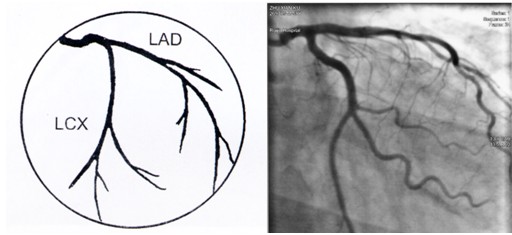

冠脉造影术简装板-绝好资料ppt

冠脉造影影像解读

冠状动脉造影,左冠状动脉造影